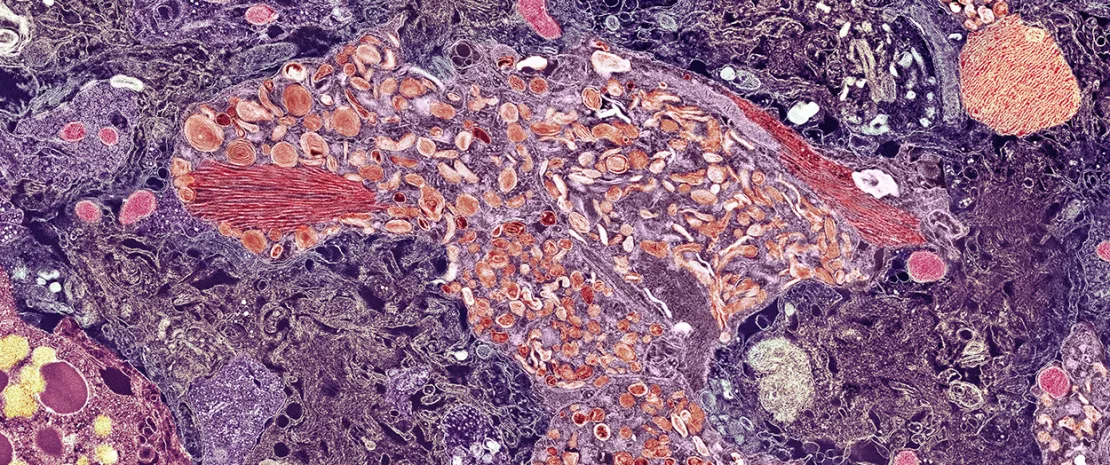

Grâce au (sidenote: Séquençage métagénomique shotgun Il s'agit d'une méthode de séquençage haute résolution qui analyse tout le matériel génétique de chaque microbe présent dans un échantillon. Contrairement aux techniques plus anciennes qui se contentent d'identifier les familles de bactéries, ce séquençage permet une identification précise jusqu'au niveau de l'espèce et révèle les gènes fonctionnels que possèdent ces bactéries. ) haute résolution sur des patients atteints de (sidenote: Trouble cognitif léger (TCL) Le TCL est un stade clinique entre le déclin cognitif attendu en cas de vieillissement normal et le déclin plus grave lié à la démence. Les personnes atteintes d'un TCL présentent des troubles perceptibles de la mémoire ou du raisonnement, mais peuvent encore accomplir la plupart de leurs activités quotidiennes, ce qui représente une opportunité cruciale pour l'intervention et l'étude. ) , un stade intermédiaire critique, les chercheurs n'ont constaté aucune différence significative au niveau de la diversité globale du microbiote intestinal par rapport au groupe témoin sain. Par contre, la grande différence se retrouve dans l'identité des acteurs. L'étude a permis d'identifier 59 espèces microbiennes spécifiques dont la présence ou l'absence avait un lien direct avec le TCL, les plaques amyloïdes et les niveaux de (sidenote: Protéine tau Tau est une protéine qui, en temps normal, stabilise le système de transport interne, les microtubules, au sein des cellules nerveuses du cerveau. Dans le cas de la maladie d'Alzheimer, elle est anormalement phosphorylée et forme des enchevêtrements neurofibrillaires à l'intérieur des neurones, entraînant un dysfonctionnement cellulaire et la mort. ) , les principales caractéristiques pathologiques de la maladie d'Alzheimer. Cela témoigne que ce n'est pas la taille de l'armée microbienne qui compte, mais plutôt les soldats spécifiques qui composent les lignes de front.

L'étude va au-delà de la simple corrélation, en identifiant des bactéries qui, en plus d'être présentes, sont fonctionnellement liées à la santé du cerveau. L'une des espèces bénéfiques identifiées, Akkermansia muciniphila, présentait une corrélation négative avec la charge amyloïde. Cela est important, car Akkermansia est connue pour produire des métabolites qui renforcent la barrière intestinale et possèdent des effets anti-inflammatoires 7. Cette recherche suggère que son rôle pourrait être encore plus direct, en influençant potentiellement le métabolisme énergétique du cerveau et en le protégeant contre l'accumulation de protéines toxiques, telles que la protéine tau.